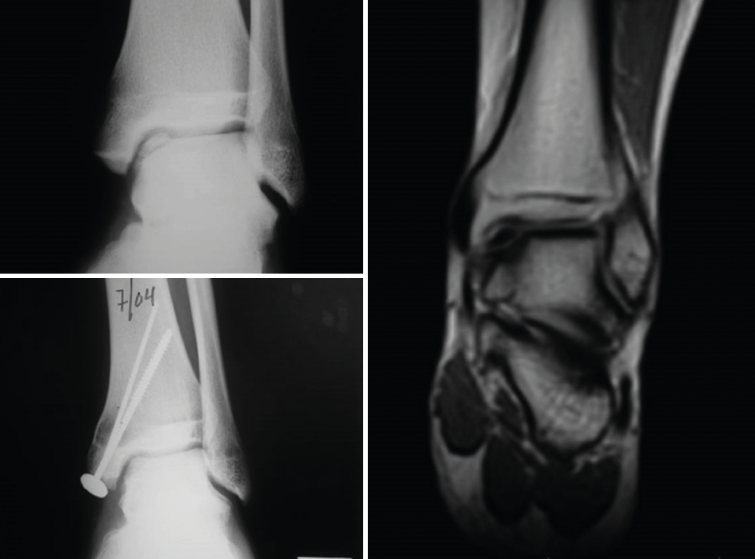

With regard to the ankle lesions, the location was in the astragalus in all 6 cases: the upper-internal quadrant in four cases and the upper-external quadrant in two.

One of these cases was the first case reported in the world of the application of the technique to ankle lesions. A malleolar osteotomy (external or internal) was performed in all 6 cases, followed by fixation with a screw. Immobilization was not used, and the patients were able to mobilize the ankle immediately. Weight bearing was avoided during 8-10 weeks.

Overall, the outcomes have been very good, with follow-up extending from 1996 (when the first case was implanted) and 2001 (when the next technical modality was adopted) to date (17-22 years of follow-up). Seventy-five percent of the patients have been able to lead a normal life, including elite sports activities in some cases. Thus, the ACI technique has yielded very satisfactory results.